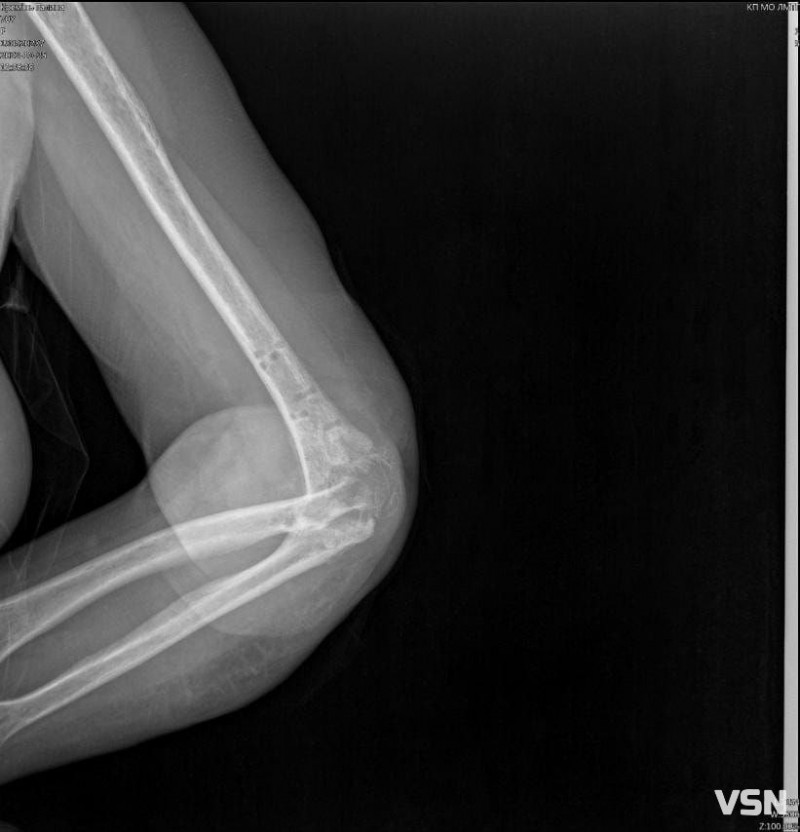

В травні минулого року, поспішаючи на роботу, Галина Кремінь впала та зламала руку, розтрощивши ліктьовий суглоб. Лікарі зробили операцію та вставили пластини, але приєдналась інфекція. Чекаючи зрощення, медики протягом чотирьох місяців рану чистили, обрізали, промивали. Проте, почався остеомієліт. Ще раз прооперували, повиймали пластини та весь метал, почистили кістки. Але суглоб встиг зіпсуватися, і тепер потребує заміни.